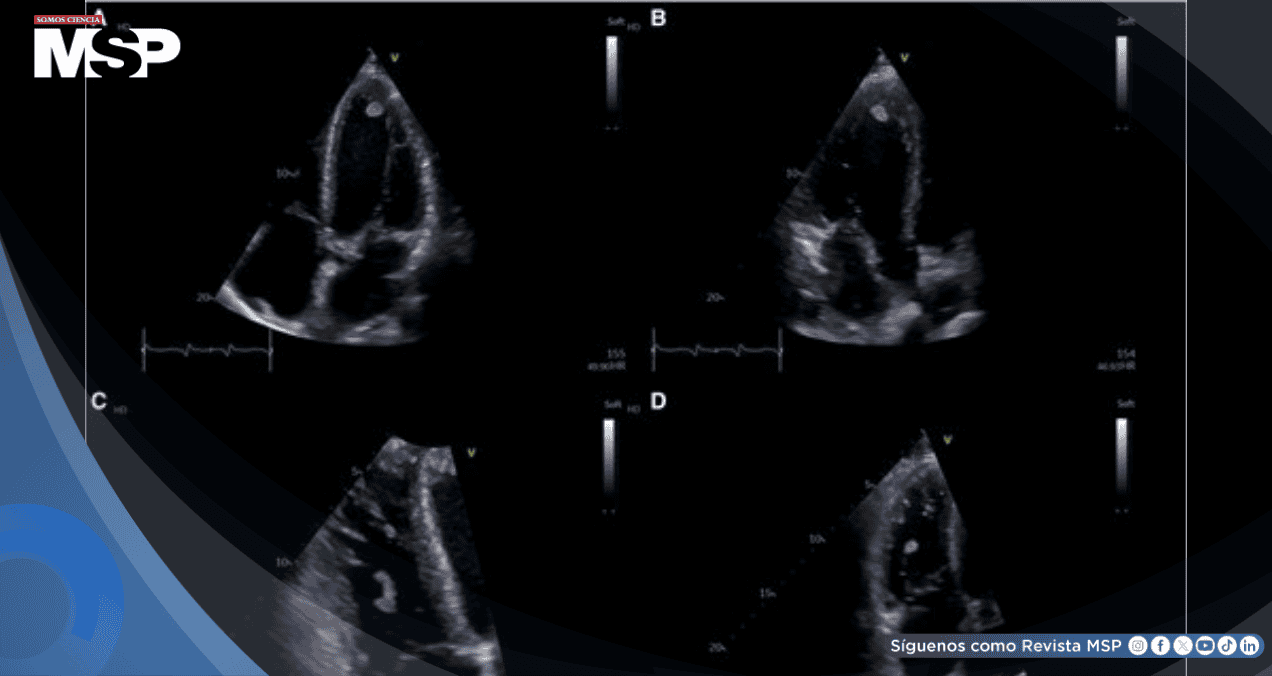

La radiografía de tórax evidenció infiltrados bilaterales difusos con pequeño derrame pleural, mientras que la ecocardiografía transtorácica documentó un ventrículo izquierdo dilatado con hipocinesia global y fracción de eyección severamente reducida del 30%.

La ecocardiografía de reingreso reveló un deterioro dramático de la función ventricular izquierda, ahora con fracción de eyección del 22%.

El hallazgo más alarmante fue la identificación de dos masas intracardíacas: una masa pedunculada adherida a las cuerdas tendinosas de la válvula tricúspide y otra localizada en el ápice del ventrículo izquierdo. A pesar del compromiso biventricular, la función sistólica del ventrículo derecho se mantenía relativamente preservada en este momento.